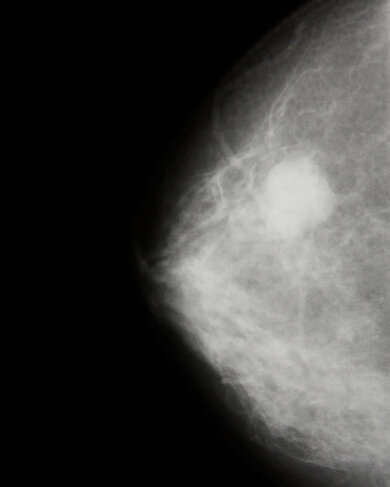

Früherkennung von Brustkrebs: Eine Mammografie mit einem verdächtigen Herd (heller, runder Fleck rechts oben)

© W&B/Fotolia